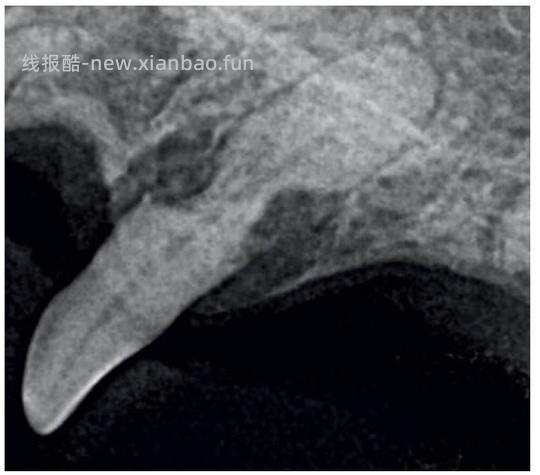

Type2(T2): 对于具有2型吸收的牙齿,牙周韧带间隙至少在某些区域变窄或者消失,部分牙齿的射线不透性降低 - 图10(b)+图12

![【科普】[养猫笔记05-医疗] 猫牙破齿细胞吸收性损伤(FORL)— 猫第二大常见疾病 - 线报酷 【科普】[养猫笔记05-医疗] 猫牙破齿细胞吸收性损伤(FORL)— 猫第二大常见疾病 - 线报酷](https://new.xianbao.fun/plus/api/image.php?imgurl=https://img2.doubanio.com/view/group_topic/m/public/p645120642.jpg)

图12 下颌前臼齿2型吸收[1]